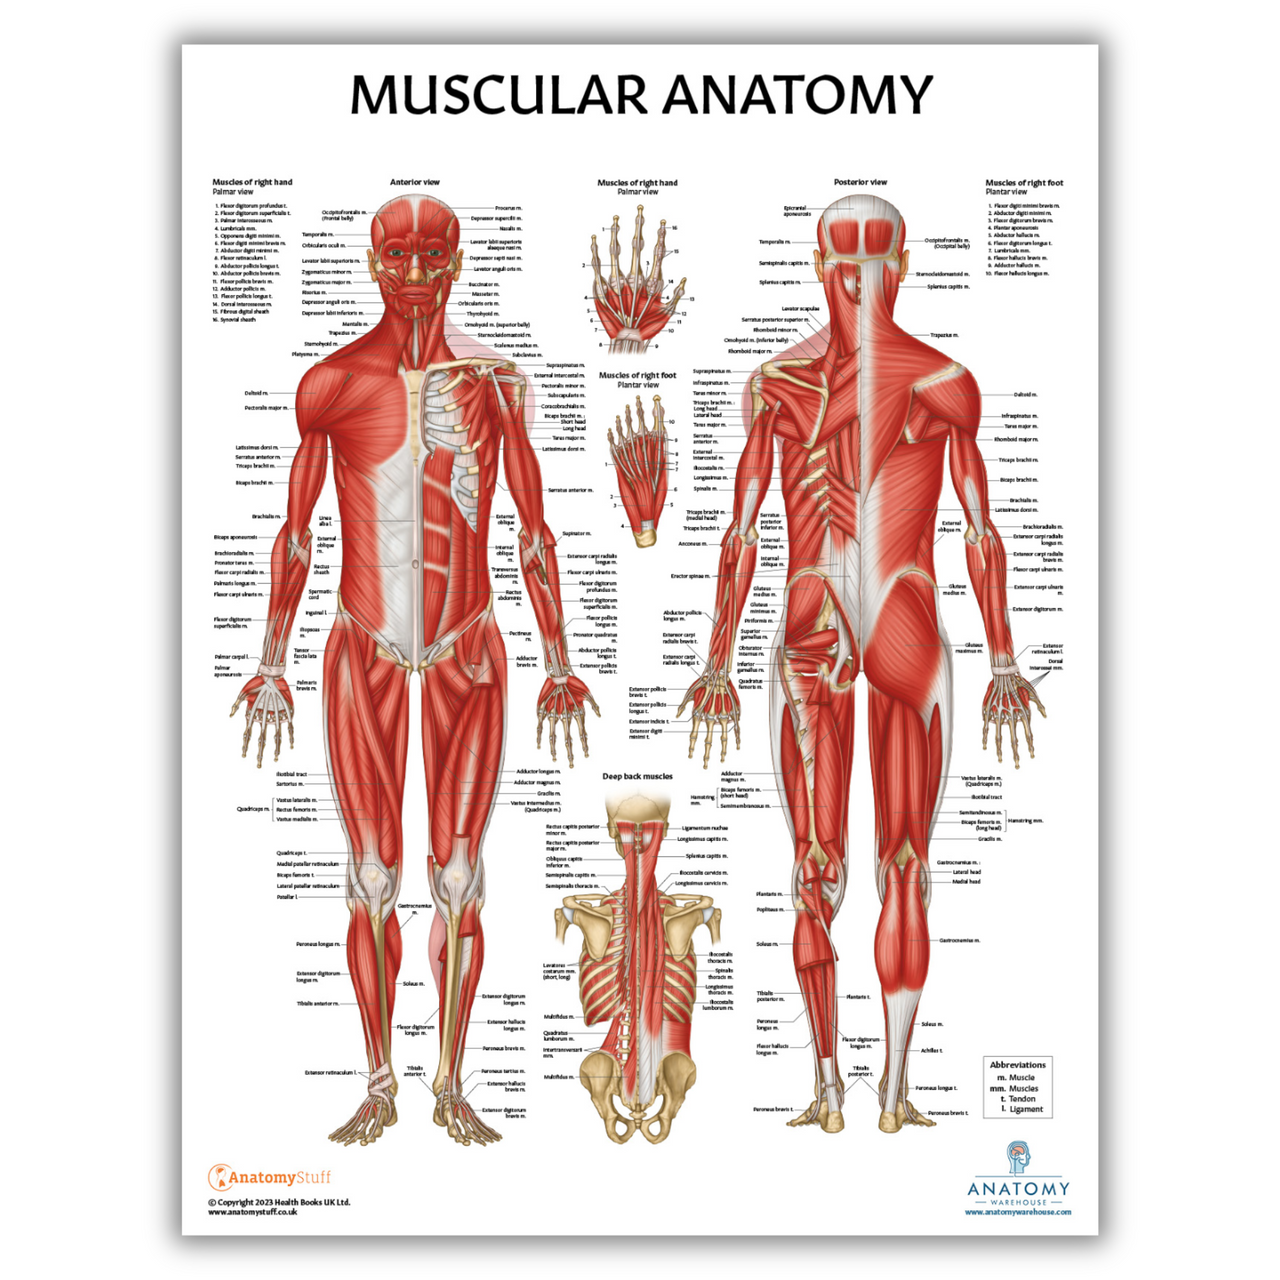

Kinesiology - Focuses on how your body movement impact on your health and physical well-beign. It encompasses various aspects like biomechanics, anatomy, physiology, and neuroscience to assess, prevent, and treat injuries and diseases.

Our Orthopedic specialists, focused on the musculoskeletal system – bones, joints, ligaments, tendons, muscles, and nerves, diagnose and treat a wide range of conditions, including fractures, arthritis, sports injuries, and congenital disorders.

Our wide range of medical services rendered by our highly experienced Medical Specialists include, but not limited to, Obstetrics and Gynaecologist, Orthopedic Surgeon, kinesiologists, Eye Care Specialists and More